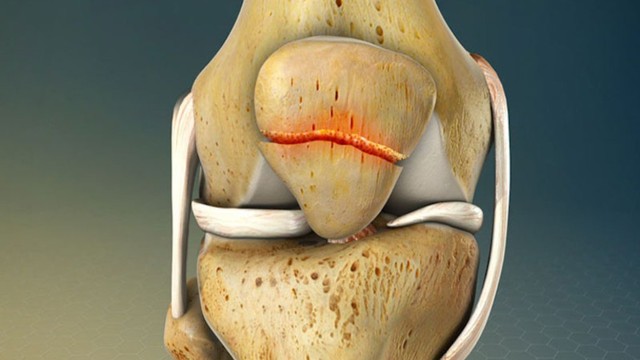

Vài nét về xương bánh chè, trật xương bánh chè là gì, biểu hiện và những biến chứng nguy hiểm chúng mang lại.

Gãy xương bánh chè thường gặp khi bệnh nhân ngã và khuỵu đầu gối xuống đất. Chấn thương này chiếm 2 - 4 % tổng số ca gãy xương. Vậy gãy xương bánh chè được định nghĩa như thế nào và làm sao để điều trị chấn thương này hiệu quả? Hãy đọc bài viết dưới đây của nhà thuốc Long Châu để tìm được câu trả lời nhé.